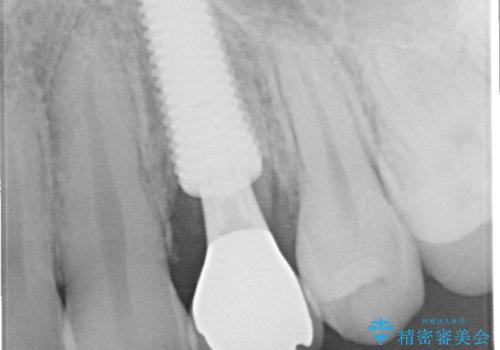

- 以前他院で、左上小臼歯(前から4番目)の虫歯治療を受けた患者様が、歯の根元から歯が折れてしまったことを主訴に来院されました。

他院では「抜歯が必要」と診断されており、「どうせ抜歯になるなら、矯正治療でスペースを閉じられないか」というご相談でした。

左上の小臼歯は健全な歯質が薄く将来的な歯根破折リスクが高く予後不良で、叢生(歯並びの乱れ)はほとんどなくご本人も歯並び自体は気になっていないという状態でした。

左上小臼歯を抜歯し、矯正治療でスペースを閉じる方法と左上小臼歯を抜歯し、抜歯即時インプラントを行う方法、保存療法を行う方法の治療期間、費用、メリット・デメリットについて説明したうえで治療期間をできるだけ短くしたいという希望があったため抜歯即時インプラント治療を選択されました。